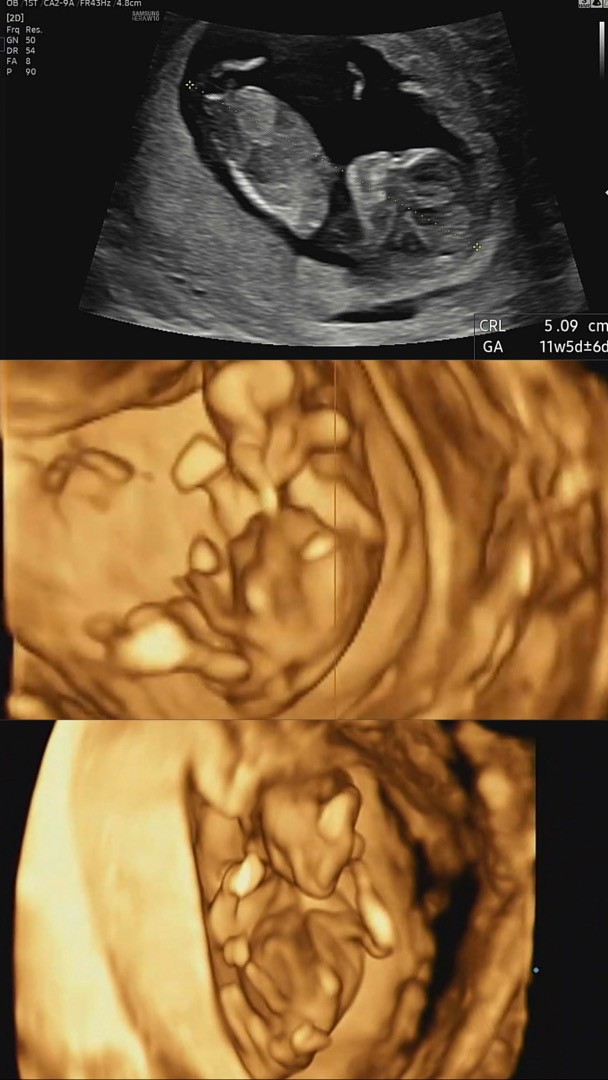

11주 성별 알수있을까요???

각도법 사진 맞나요 ?? 성별이 뭘까요 넘 궁금하네용

11주는 알 수 없는걸로 알아요 ㅎㅎㅎ 12주때 튀어나와있었는데 원장님이 지금은 모른다고 들어길 수도 있다고 하시더라구용